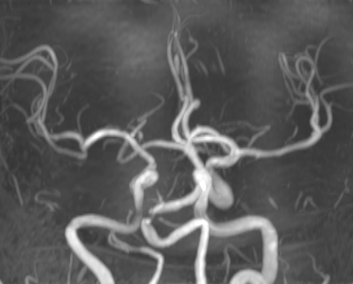

颅内血管可见多发动脉瘤,颅内多发血管狭窄,尤其基底动脉重度狭窄